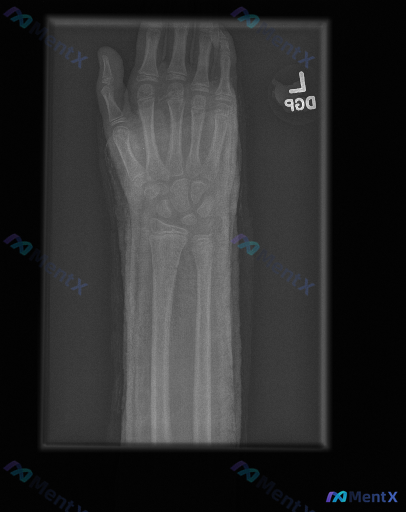

整理到一组影像资料和配套的分析背景,想和大家讨论下这种情况的思路: - 影像来源:左手正位X光片 - 常规阅片所见: - 各腕骨、掌骨、指骨骨皮质轮廓尚完整,未见明显骨折线、脱位或半脱位; - 骨密度、关节间隙未见明显异常; - 关节面、软骨下骨、软组织影也未见明确的典型异常改变(如骨赘、弥漫肿胀、...

整理到一份未成年人左手腕及前臂正位X光片的影像资料,想跟大家讨论一下阅片判断的逻辑。 基本情况 - 受试者:未成年人(影像提示骨骺尚未闭合) - 检查部位:左手腕及前臂(正位) 影像观察要点(摘要) 1. 骨骼发育:可见明显骨骺板(生长板),骨化中心发育与年龄相符 2. 骨折筛查:桡骨/尺骨远端皮质...

整理到一份左手正位X光片的影像资料与临床背景: 影像表现概要 - 诸掌骨、指骨、腕骨骨皮质连续,未见明确骨折线、脱位或明显骨质破坏; - 各关节间隙宽度大致正常,关节对位良好,未见明显退行性变; - 拇指掌指关节尺侧可见一枚圆形边界清晰的高密度影,报告考虑为生理性籽骨; - 软组织影轮廓尚自然,未见...